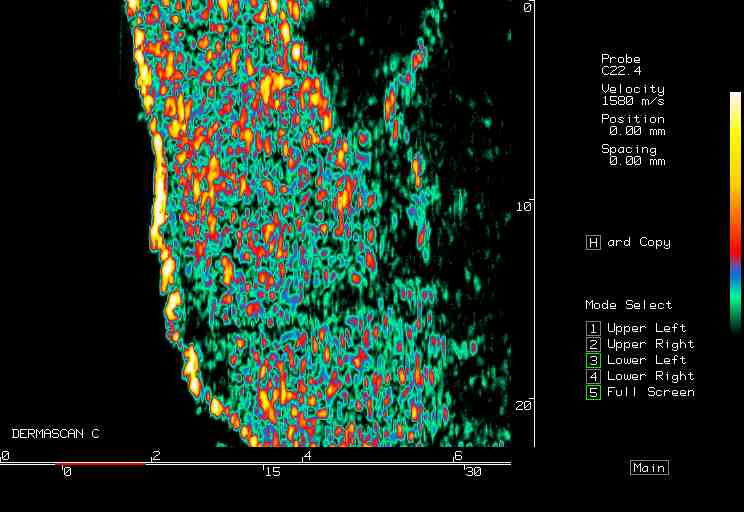

20 MHz 2D images

| Reactions |  Irritant reaction |

Patch test, back |

Insect bite |

Allergic reaction |